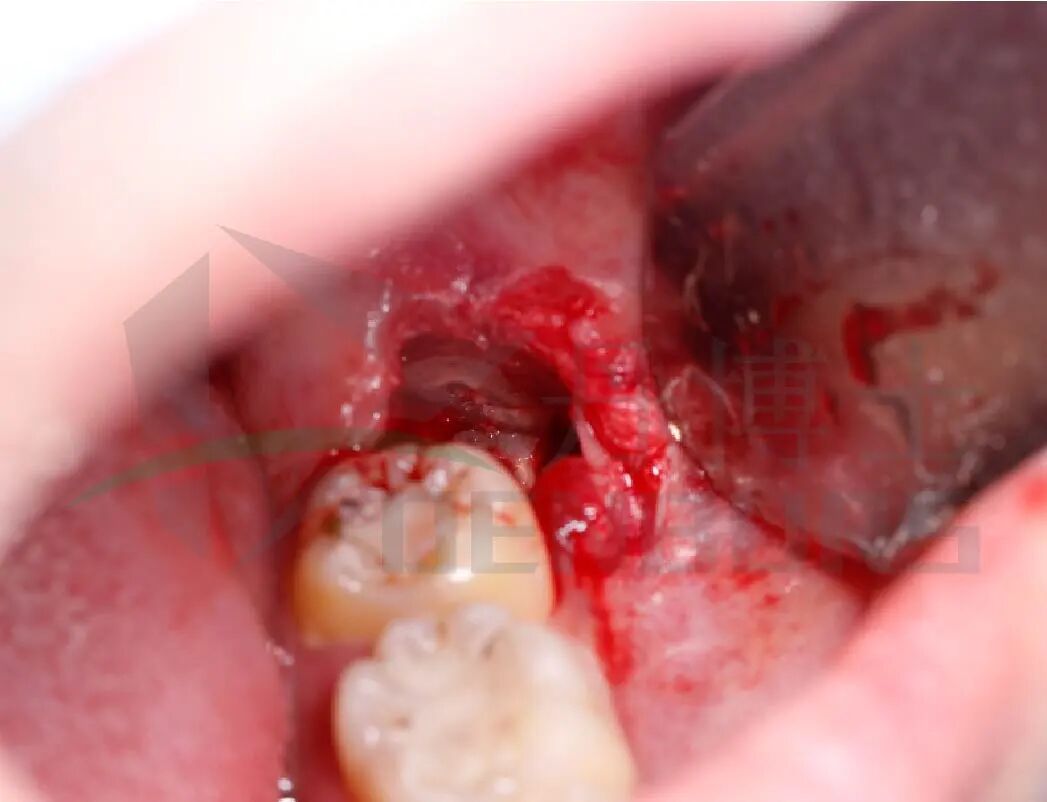

1)麻醉与翻瓣

局麻下切开并形成改良三角瓣,暴露患牙,解除软组织阻力。